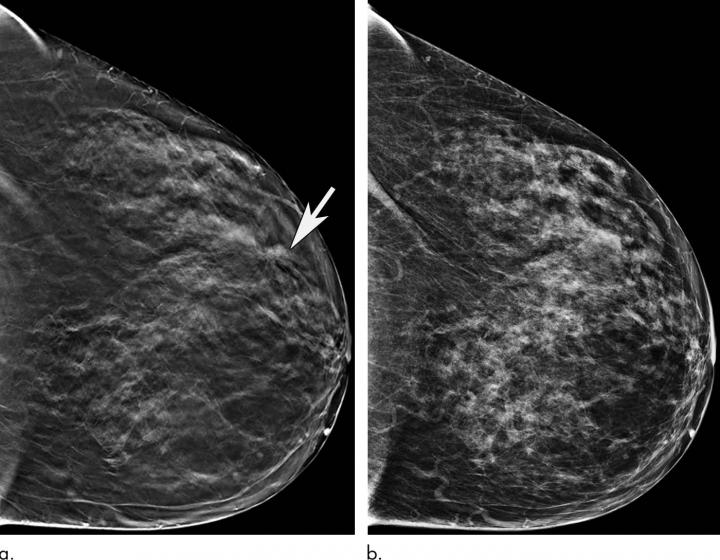

عکس ماموگرافی زنان

بعد از انجام ماموگرافی عکس ماموگرافی یا سی دی آن به شما تحویل داده می شود. عکس ماموگرافی بر اساس نوع دستگاه ماموگرافی و نمای تصویر برداری ظاهر متفاوتی دارد. نماهای مختلف ماموگرافی به تشخیص دقیق تر ضایعه کمک می کند. در ادامه چند نوع عکس ماموگرافی را مشاهده می کنید.